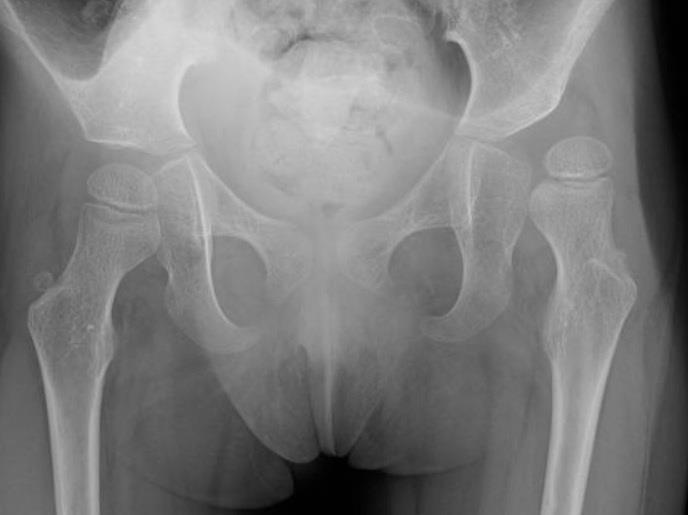

Hipdislocation

Regular follow-up, including pelvic Xrays from an early age, and early rehabilitative treatment are essential to prevent hip dislocation in children withseverecerebralpalsy.